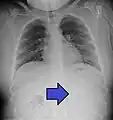

AP X ray showing a 9mm battery in the intestines